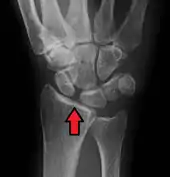

X-ray images indicate scapholunate ligament instability when the scapholunate distance is more than 3 mm, which is called scapholunate dissociation.[7] A static scapholunate instability is generally readily visible, but a dynamic scapholunate instability can only be seen radiographically in certain wrist positions or under certain loading conditions, such as when clenching the wrist, or loading the wrist in ulnar deviation.[6]

In order to diagnose a SLAC wrist you need a posterior anterior (PA) view X-ray, a lateral view X-ray and a fist view X-ray.[8] The fist X-ray is often made if there is no convincing Terry Thomas sign. A fist X-ray of a scapholunate ligament rupture will show a descending capitate bone. Making a fist will give pressure at the capitate, which will descend if there is a rupture in the scapholunate ligament.

Static scapholunate dissociation